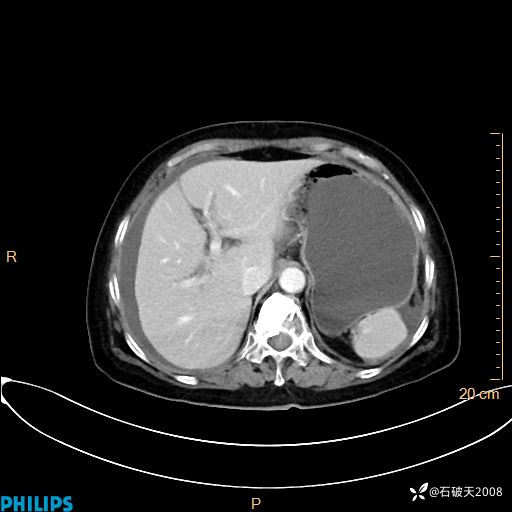

MIP